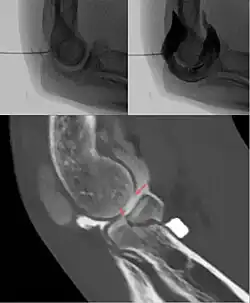

Gleichzeitig sind mit der Entwicklung der Magnetresonanztomographie und der Computertomographie neue Einsatzgebiete für die Arthrographie entstanden. Hierbei dient die Kontrastmittelinjektion in das Gelenk der Entfaltung der Gelenkkapsel und somit der besseren Beurteilbarkeit der ansonsten eng aufeinanderliegenden Weichteilstrukturen. Des Weiteren lassen sich manche Verletzungen des Knorpels, der Gelenkscheiben (Menisci), der Gelenkkapsel und der Gelenkbänder nur mit Hilfe einer Kontrastmittelinjektion sicher beurteilen. Insbesondere in der Diagnostik des Schultergelenks und der Handwurzel ist die Arthrographie mit anschließender Kernspintomographie oder Computertomographie wieder ein Standardverfahren geworden.